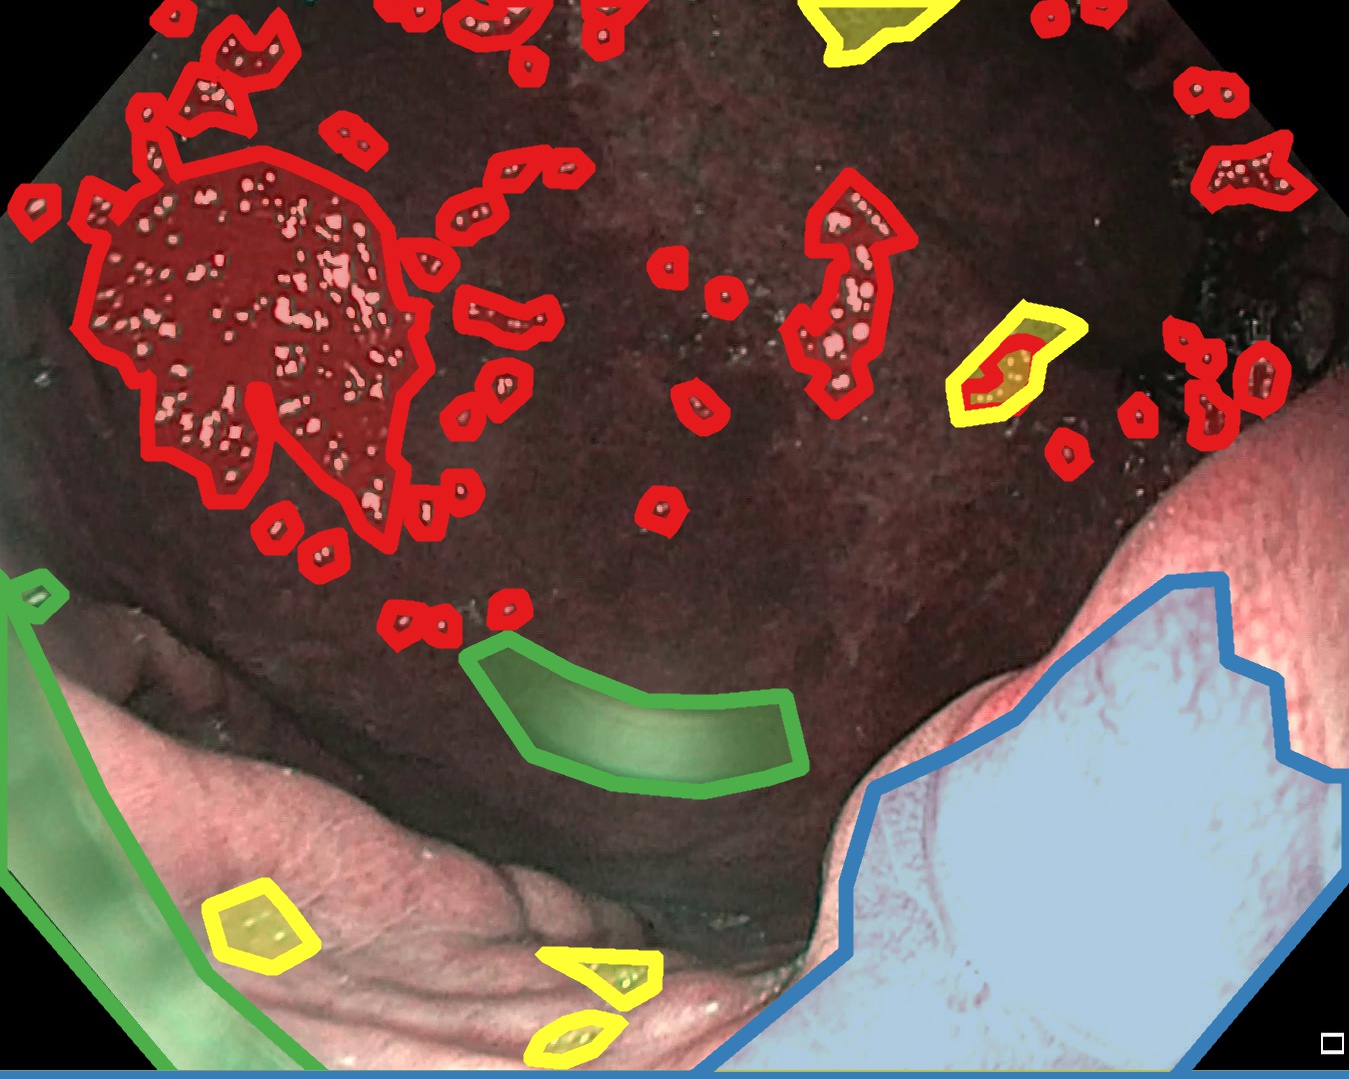

Examples for bounding box annotations for detection are shown in Fig. 2. It can be observed that while multiple boxes are annotated for several small specular areas; contrast, blur and instrument have relatively larger areas. Due to the overlap between two or more classes, the annotation by experts varied. This was minimized by following the detailed annotation protocol above. For semantic segmentation, a larger area mask was preferentially used to delineate locally very cluttered small specularity artifacts (see Fig. 3).